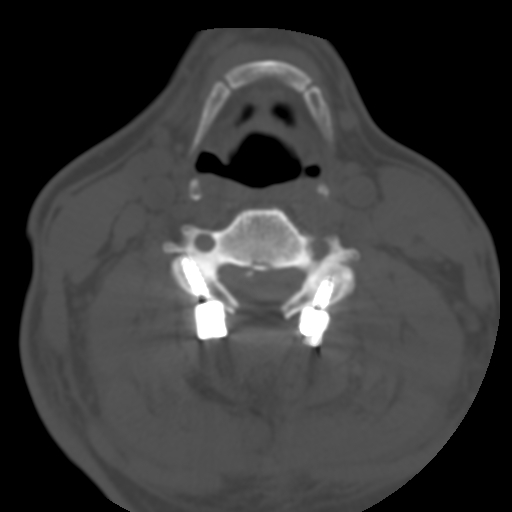

术后CT见减压充分,螺钉位置良好